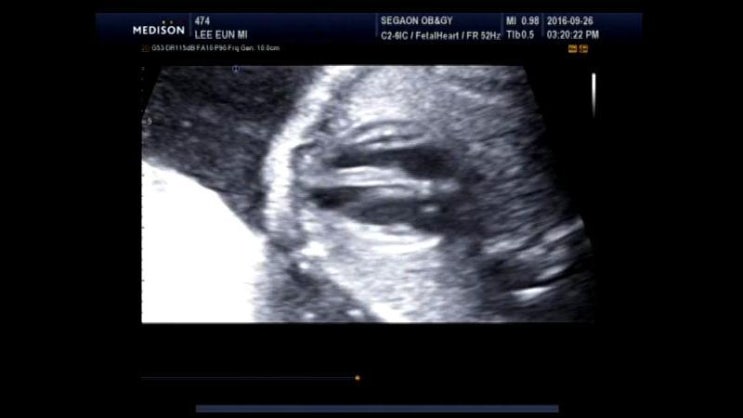

2016년 9월 26일 오복이 23주 3일차

4주만에 다시 만나 오복이~ 오늘은 2차 정밀 초음파 검사하는날! 우리 오복이 손가락 발가락...